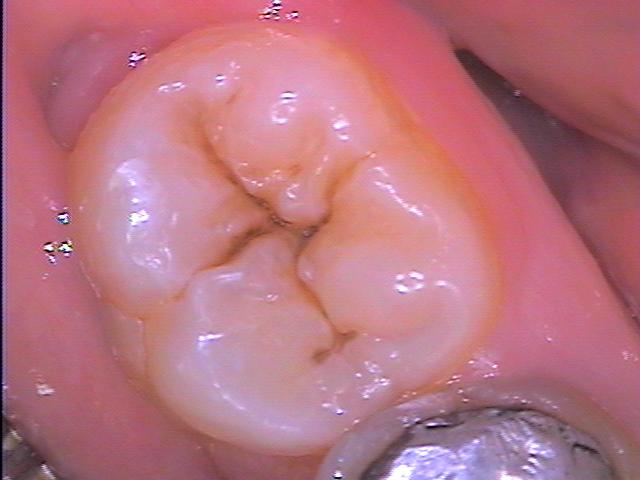

Снимка на първичен кариес върху оклузалната повърхност на моларен зъб. Всеки един пациент е възможно сам да извърши оглед на своите зъби и при наличие на кухини да отиде на зъболекар; разбира се, срещат се и кариеси на труднодостъпни места, които се виждат много трудно дори и от стоматолога. В много случаи се налага дори рентгенография, която да послужи за диагностика на кариеса - най-вече в междузъбните пространства, в които огледът не е възможен.